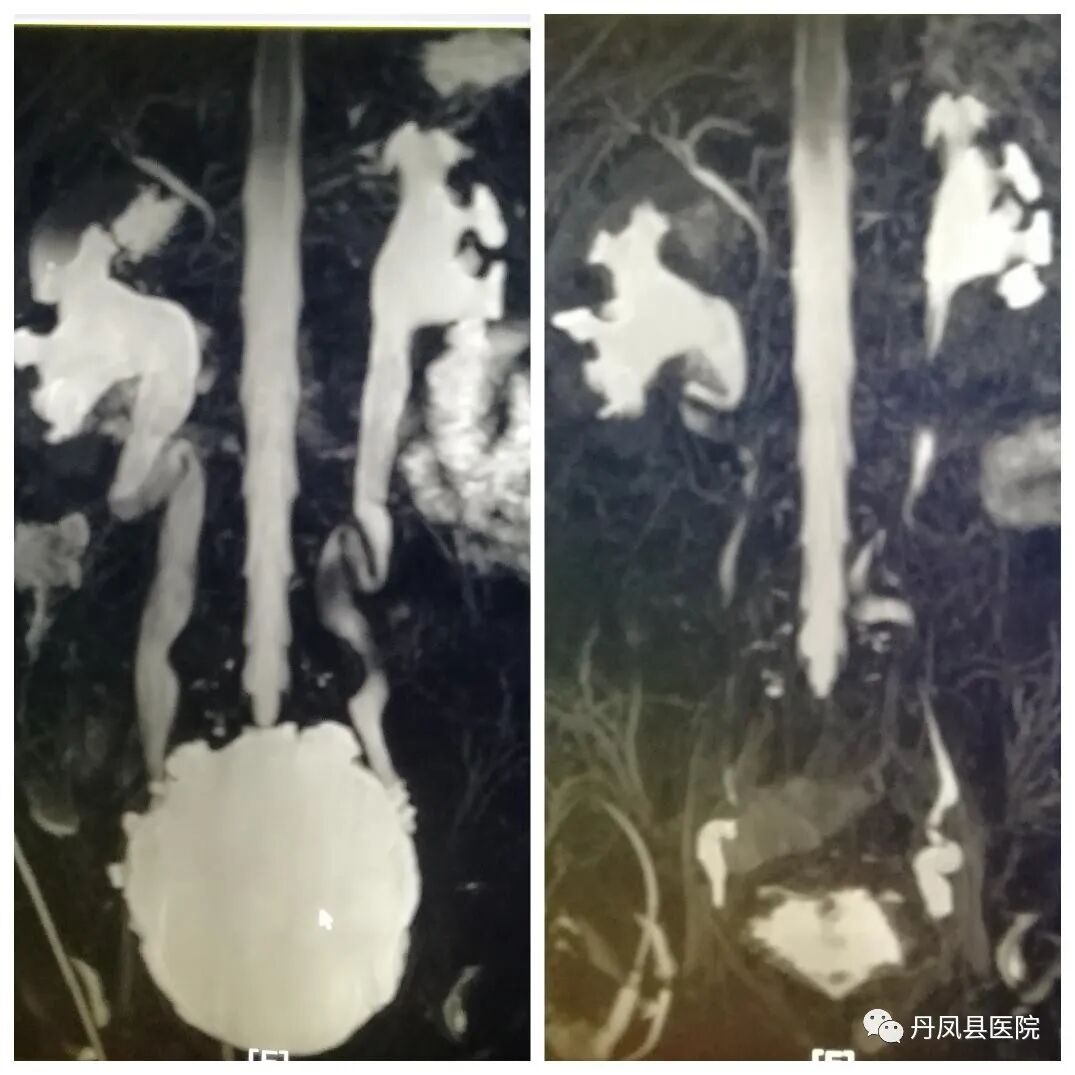

![泌尿系水成像.jpg]()

泌尿系水成像(MRU)